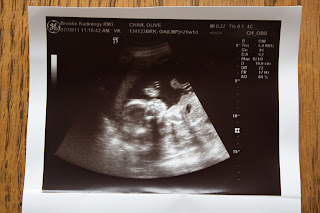

Here are a couple pics from the ultrasound.

A perfect little leg and foot!